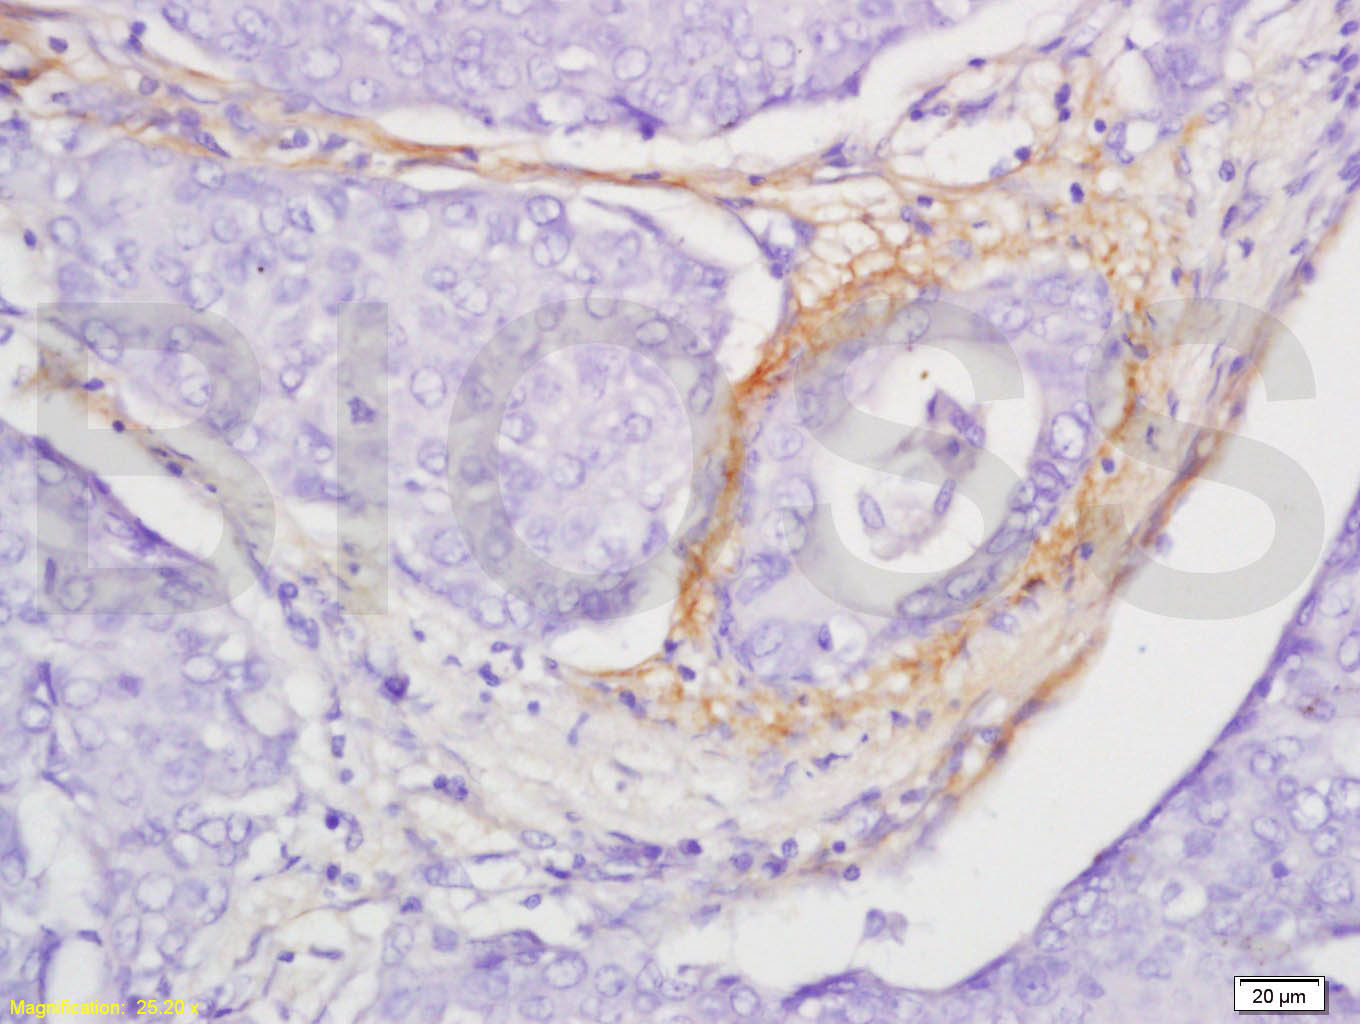

Paraformaldehyde-fixed, paraffin embedded (Rat brain); Antigen retrieval by boiling in sodium citrate buffer (pH6.0) for 15min; Block endogenous peroxidase by 3% hydrogen peroxide for 20 minutes; Blocking buffer (normal goat serum) at 37°C for 30min; Antibody incubation with (CCL4) Polyclonal Antibody, Unconjugated (bs-1046R) at 1:400 overnight at 4°C, followed by operating according to SP Kit(Rabbit) (sp-0023) instructions and DAB staining.